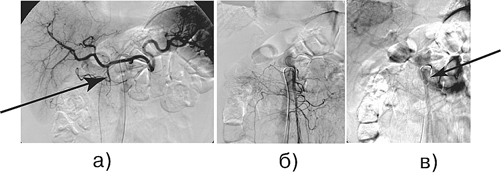

Рисунок 5. Больной М., 72 года. Диагноз: рак головки поджелудочной железы с инвазией верхней брыжеечной вены, T 4 N 1 M 0 :

а — целиакография: артериальная фаза, ригидность желудочно-двенадцатиперстной артерии; б — верхняя мезентерикография, артериальная фаза; в — возвратная мезентерикопортография: циркулярное сужение проксимального отдела верхней брыжеечной вены.В дальнейшем выполнена ГПДР с циркулярной резекцией верхней брыжеечной вены